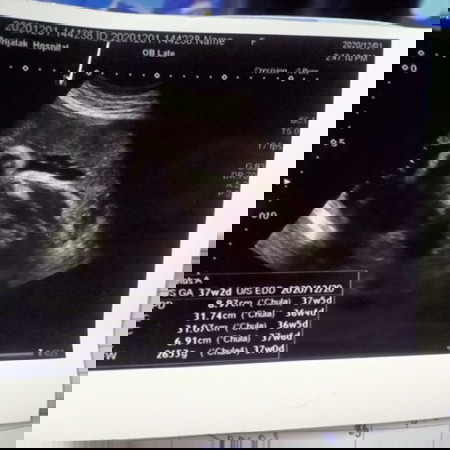

❤️หญิงหรือชาย❤️

แม่ๆช่วยดูหน่อย หญิงหรือชาย❤️

ชาย